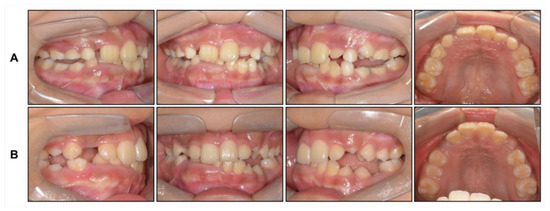

Intraoral examination showed anterior crossbite and severe deep bite with a −2.0 mm overjet and 7.0 mm overbite with no functional shift. The patient exhibited severe crowding on maxillary dentition along with a maxillary transverse deficiency. The mean difference in the width of the maxillary and mandibular first molars at the age of 8 years has been reported to be 6.4 mm, whereas in our patient, it was only 4 mm [19]. He showed a 1 mm deviation of the mandibular dental midline toward the left side. Hypertrophy of the mandibular right anterior alveolar bone was clear, which had led to the canting of the mandibular anterior teeth.

Based on this, we decided to start an orthopedic treatment and closely follow up the hypertrophic region. We placed a bonded rapid palatal expansion appliance with a hook for the face mask, and the screw was turned once a day for 2 weeks. The separation of the midpalatal suture was confirmed, and the face mask was set up with the instruction of wearing it for at least 14 h a day. After 5 months, the crossbite was relieved, and the anteroposterior jaw relationship was improved. Nevertheless, there was still a lack of space for the eruption of permanent teeth on the maxillary dentition (Figure 4A). We stopped the use of the face mask and set up an active removable appliance on the maxilla to gain space. After 18 months, sufficient space was made on the maxillary dentition, and we decided to finish the phase 1 treatment (Figure 4B and Figure 5).

Figure 4. Intraoral photographs: (A) After face mask treatment; (B) At the end of phase 1 treatment.